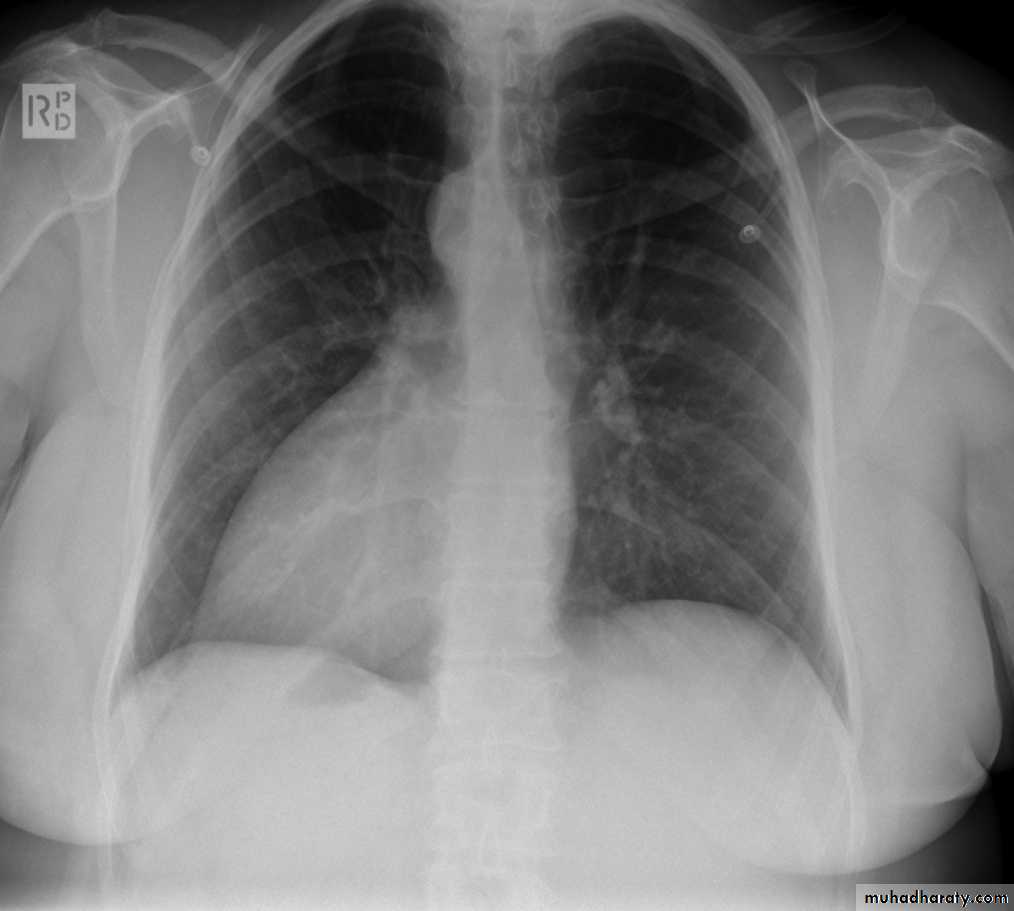

EmphysemaCXR of adult female ,PA view shows:Flattening of the hemidiaphramsWidely spaced ribsTenting of the diaphramAbnormal shape of the heart (tubular)Increased and irregular radiolucency of the lungsVascular changes, paucity of blood vessels (absent pulmonary markings in the outer 1l3 of the lung fieldsThere is an emphysmatous bulla (area devoid of lung markings more than 1 cm) in the hilar area of the right lung .